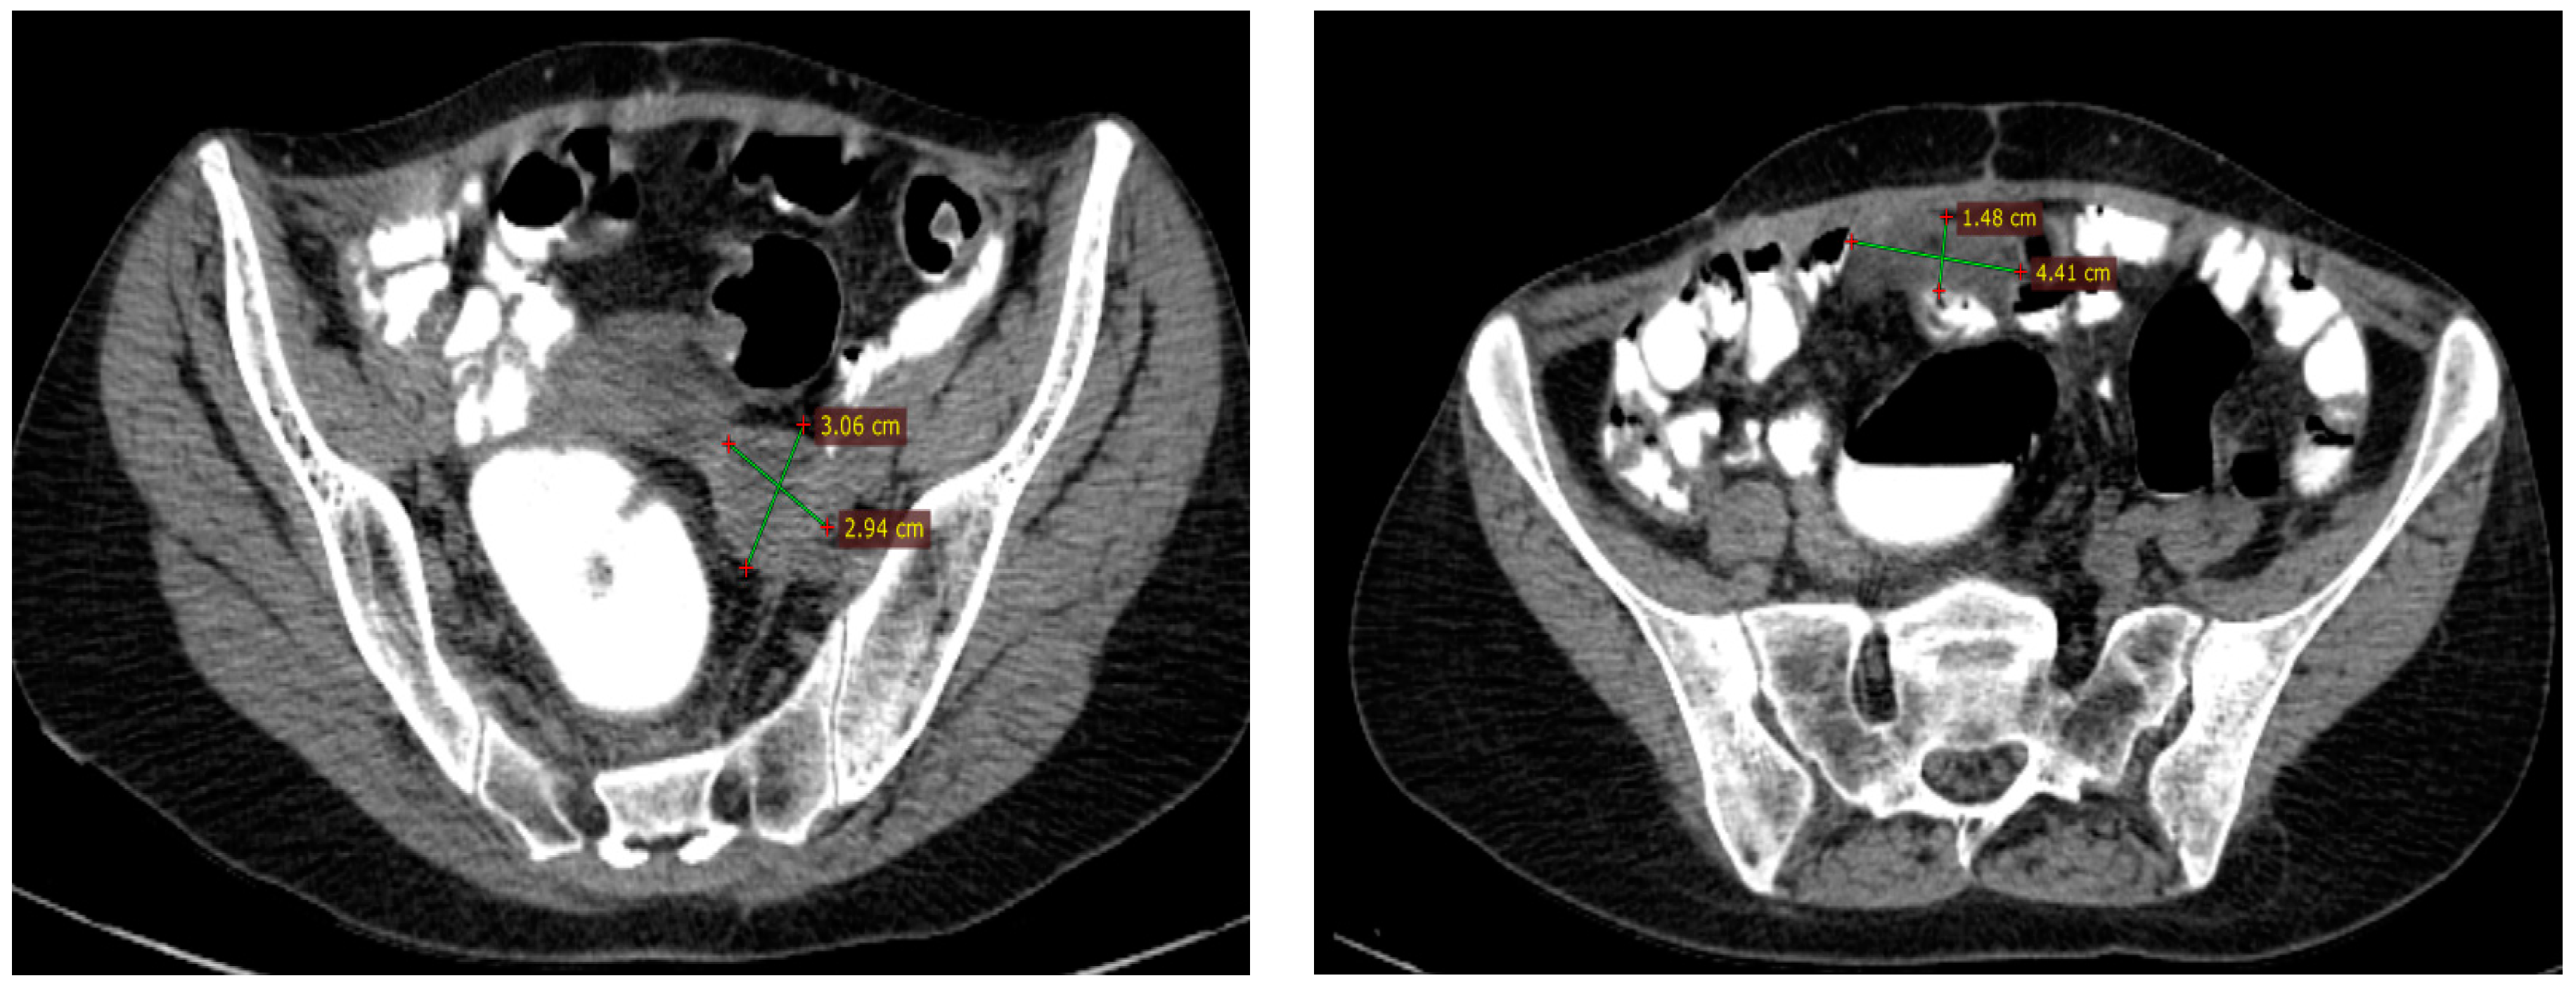

In April 2016, a CT scan (Figure 3) revealed progressive disease by a left external iliac lymph node of 30/29 mm, with discrete ureteral dilation and an inframesocolic peritoneal nodule of 15/44 mm. The tumor was considered platinum-sensitive, and between June and October 2016, the patient received three cycles of Carboplatin (AUC 5) plus Paclitaxel (175 mg/m2) and then one cycle of Carboplatin (AUC 5) alone due to side effects (allergic reaction to Paclitaxel, thrombocytopenia grade 1, and anemia grade 2); after cycle four, the patient requested interruption of chemotherapy.

Figure 3.

Second radiological assessment: April 2016 CT scan showing progressive disease with a new lesion—inframesocolic nodule of 15/44 mm.

In October 2016, a CT scan of the abdomen and pelvis showed a partial response according to RECIST v1.1 based on a decrease of 35% of the target lesions (the external iliac tumor mass now measured 26/18/31 mm and the inframesocolic nodule had disappeared). Laboratory tests showed a normal level of CA-125 and grade 3 anemia (Table 1).

Maintenance therapy with Olaparib 400 mg twice daily was started in November 2016 and continued throughout December 2023, with the best response of complete response on regular imaging assessments (Figure 4). The main side effects were asthenia grade 1 and nausea grade 1, successfully treated with metoclopramide 10 mg bid. At the last available clinical examination (December 2023), the patient had a good performance status (ECOG PS 0) and no symptoms. The visual summary of the outcomes over time is depicted in Figure 5.

Figure 4.

The complete response was assessed based on a CT scan from February 2020.